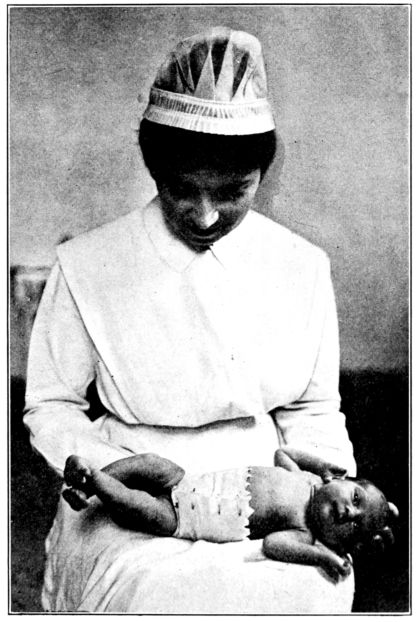

| 158. | Abdominal binder applied over cord dressing | 471 |